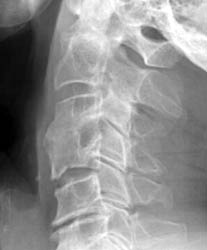

Latera C-spine - Click on the image to enlarge Conservative management utilizing a rigid cervical collar was prescribed for 6 months. 5 months later bony healing has occurred with incorporation of the graft.